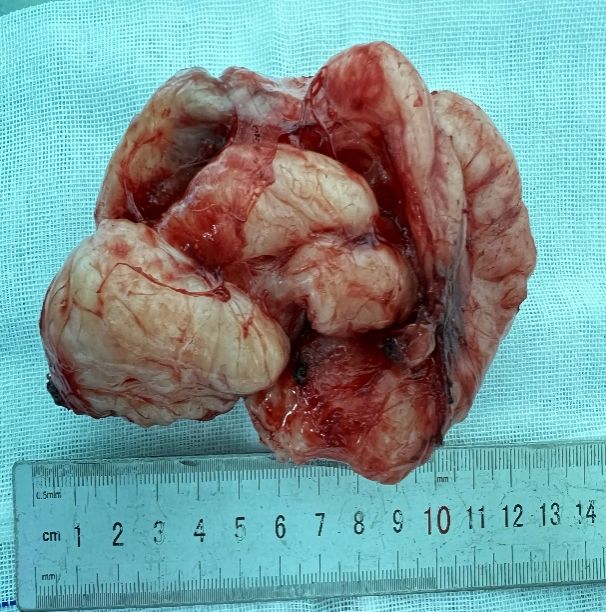

在2024年10月21日,姜建涛主任医师、李建忠副主任、赵丹文医师为小张实施了手术治疗,术中先尝试胸腔镜手术,腔镜下可见食管下段至贲门巨大隆起性病变,姜主任评估后认为腔镜下操作困难大,遂将操作孔延长至5cm行手术,术中发现肿瘤环食管周生长,完整剥除及其困难,但考虑小张年轻,未避免切除食管而对小张以后的生活造成影响,姜主任团队仔细操作,尽可能为小张保住食管,在姜主任及其团队的精心操作下,手术顺利,手术仅历时一个多小时,便将肿瘤完整剥除,剥除下来的肿瘤长径达到了快13cm,试水检查食管粘膜未损伤。在术后第一天查房的时候小张已经能下地活动了,激动的拉着姜主任的手,感谢姜主任为她成功实施手术并保住了食管,感叹姜主任的高超技艺,现小张一切恢复顺利,已康复出院。